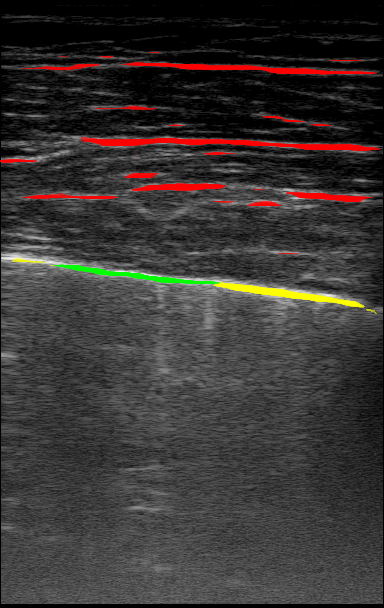

The performance of our models in segmenting specific lung ultrasound features is represented in Figure 3. None of the models demonstrated a consistent advantage across all features, highlighting that each model possessed relative strengths and weaknesses depending on the visual characteristics of the target. For example, the model trained with 100% confidence labels performed best at segmenting features that typically appear as intensely bright, relatively isolated large areas, such as certain vertical artifacts (B-lines) and sub-A lines. These features may be easier to delineate due to their high contrast and limited overlap with surrounding structures. In contrast, models trained with lower thresholds, such as the 50% confidence model, performed relatively well on pleural features, indicating that this model is potentially better at identifying structures that are less uniformly bright or more linear and contiguous, such as the pleural line itself, which requires recognizing a specific pattern along a boundary. Across the models, there was a general tendency to struggle with thin, elongated structures like a sharp pleural line and fine sub-A lines, while performing better on features that occupy larger areas of the image or have a more amorphous appearance, such as a thickened, "fuzzy" pleura or fascia bands in the chest wall.

Figure 4 shows example segmentation outputs for the same test example shown in Figure 1. Each image represents the segmentation output of a model trained with the relevant confidence threshold. Similar to the expert labels, the segmented clinical features tend to get more refined as the confidence threshold increases. The 100% model tends to over-segment features, while the 100% model misses some features entirely, as expected.